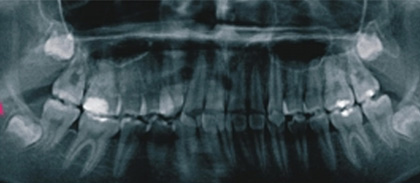

智慧齒萌發時常推擠前面牙齒,造成前面牙齒不正常之移動